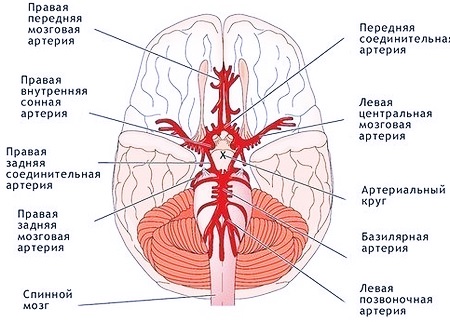

Особенности и диагностика левостороннего кровотока